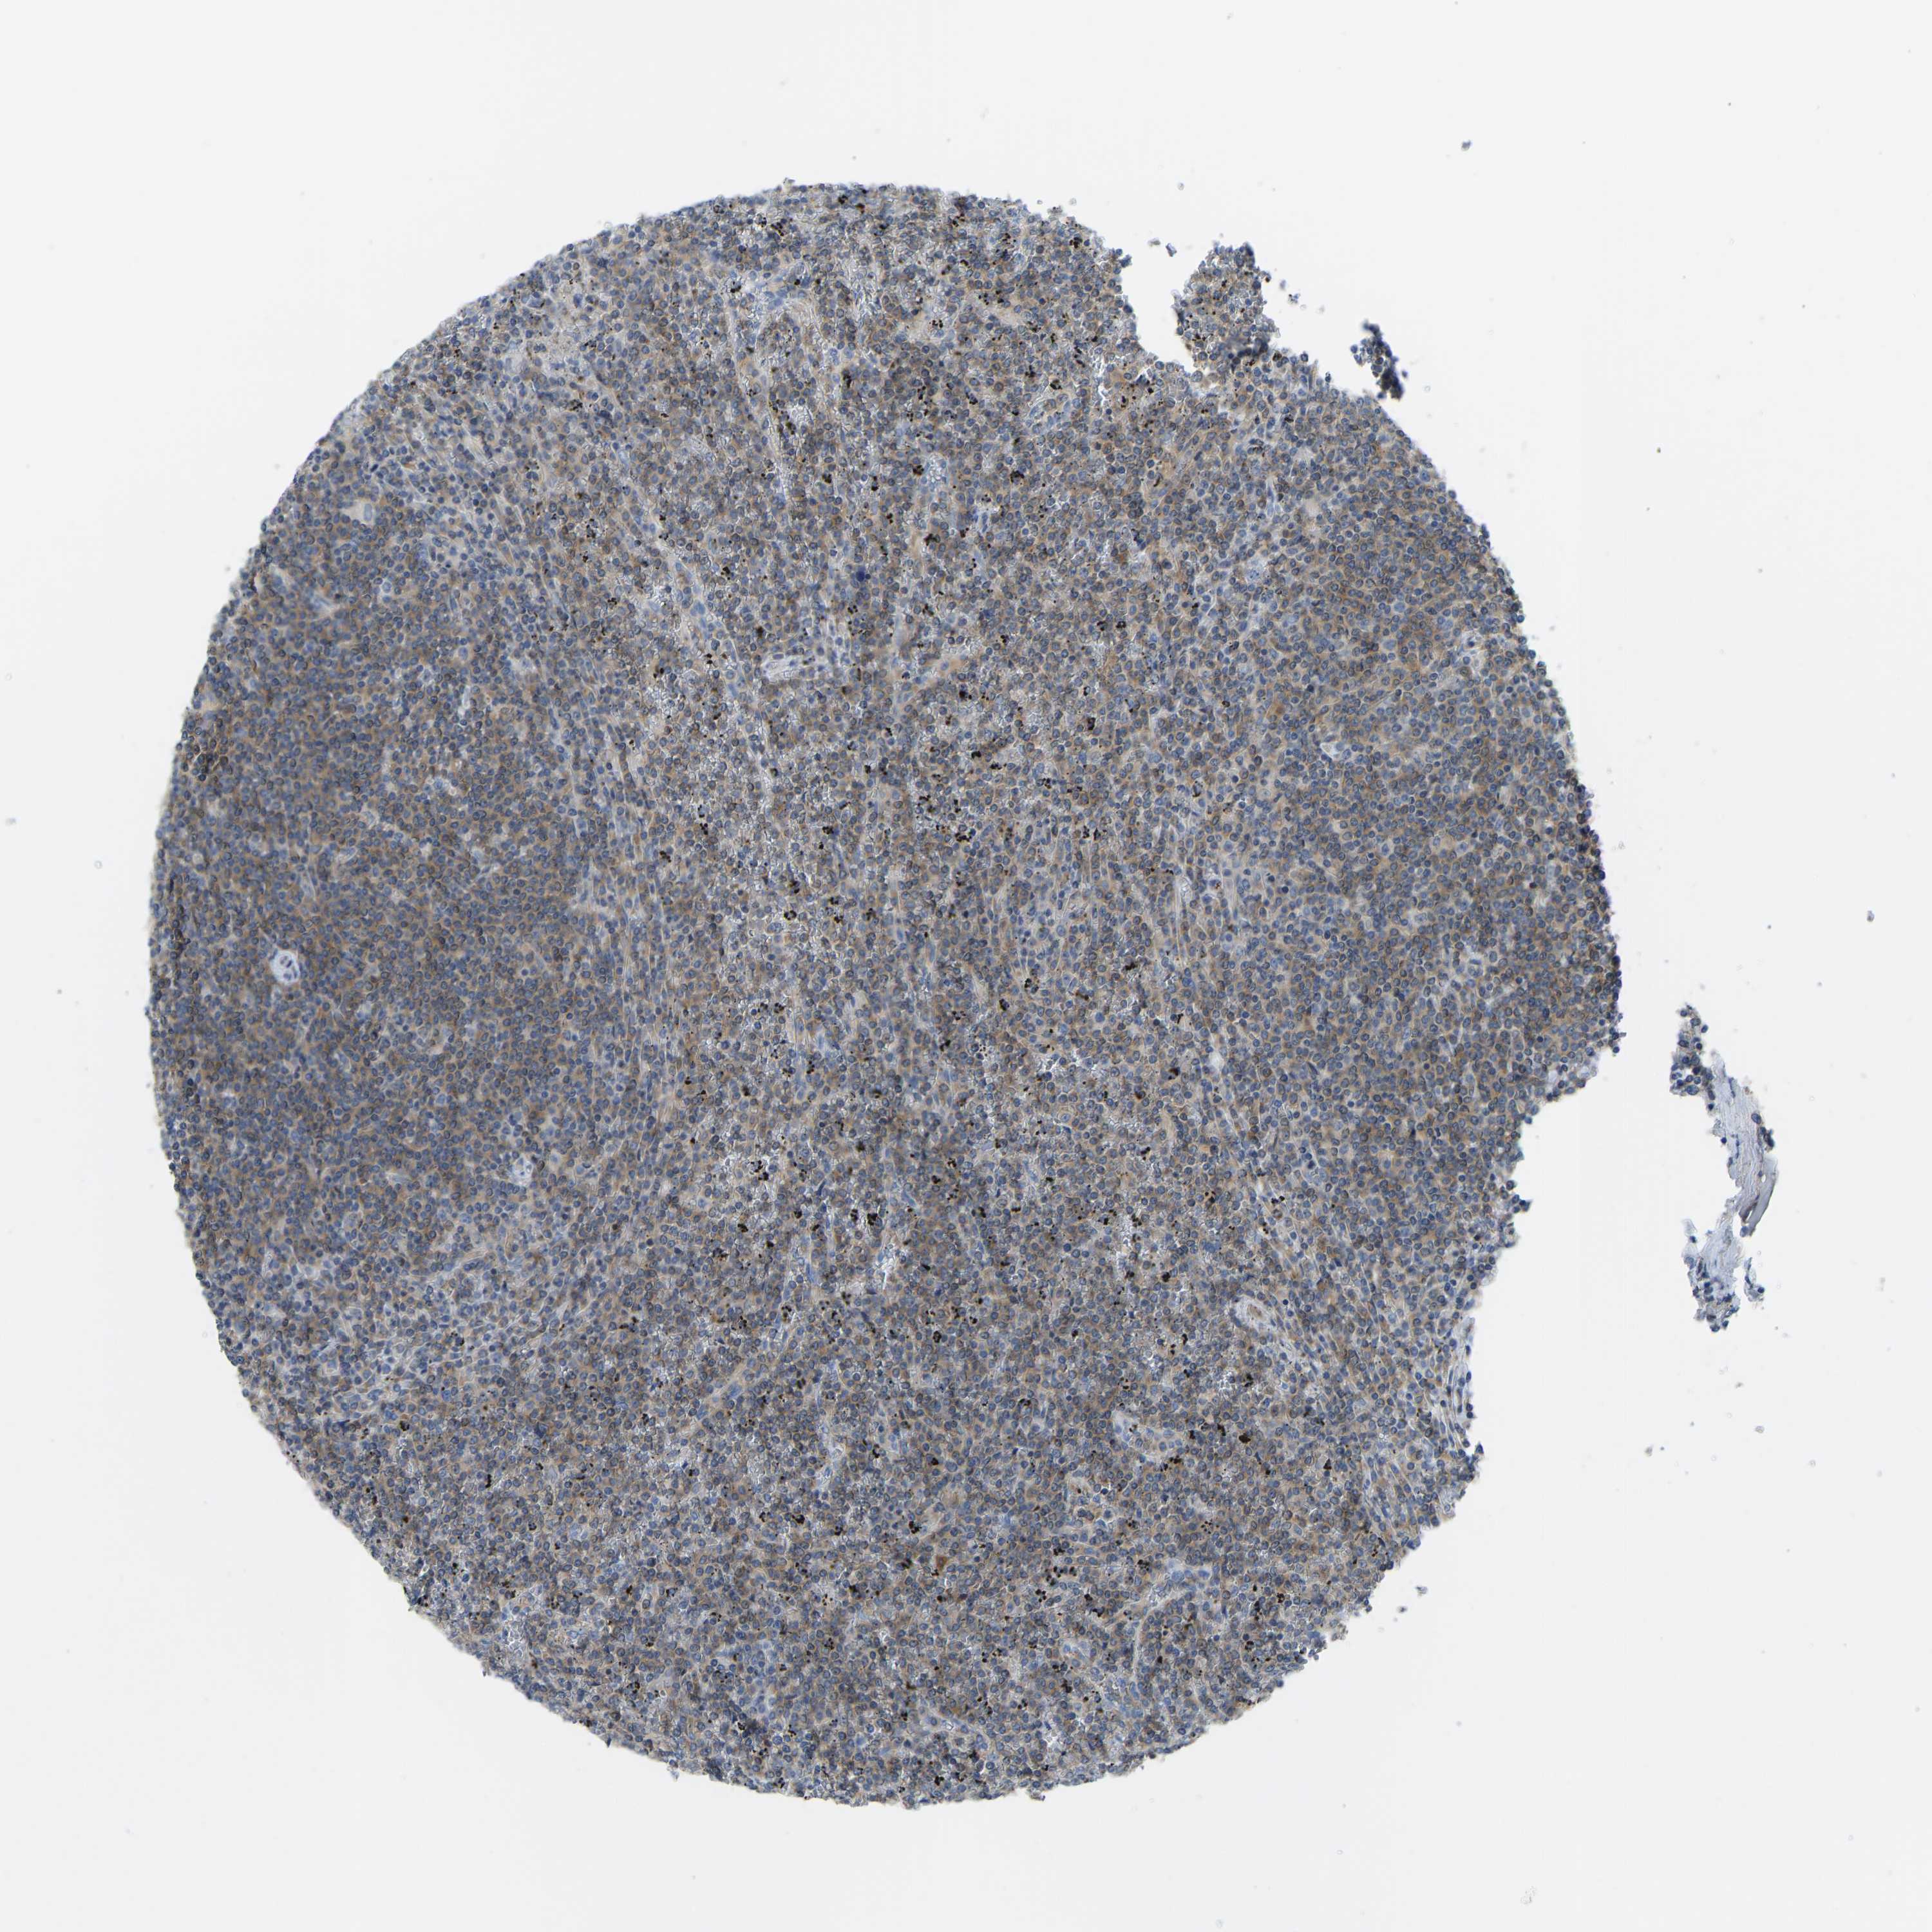

CANCER LYMPHOMA Show tissue menu

LYMPHOMA - Protein expressioni

A mouse-over function shows sample information and annotation data. Click on an image to view it in a full screen mode. Samples can be filtered based on level of antibody staining by selecting one or several of the following categories: high, medium, low and not detected. The assay and annotation is described here.

Antibody stainingi

Antibody staining in the annotated cell types in the current human tissue is reported as not detected, low, medium, or high, based on conventional immunohistochemistry profiling in selected tissues. This score is based on the combination of the staining intensity and fraction of stained cells.

Each image is clickable and will lead to virtual microscopy that enables deeper exploration of all samples and also displays staining intensity scores, fraction scores and subcellular localization as well as patient and tissue information for each sample.

Antibody HPA012778

Antibody CAB018581

Staining

High

Medium

Low

Not detected

Intensity

Strong

Moderate

Weak

Negative

Quantity

>75%

75%-25%

<25%

None

Location

Nuclear

Cytoplasmic/membranous

Cytoplasmic/membranous,nuclear

Hodgkin's disease, NOS

Malignant lymphoma, non-Hodgkin's type, High grade

Malignant lymphoma, non-Hodgkin's type, Low grade